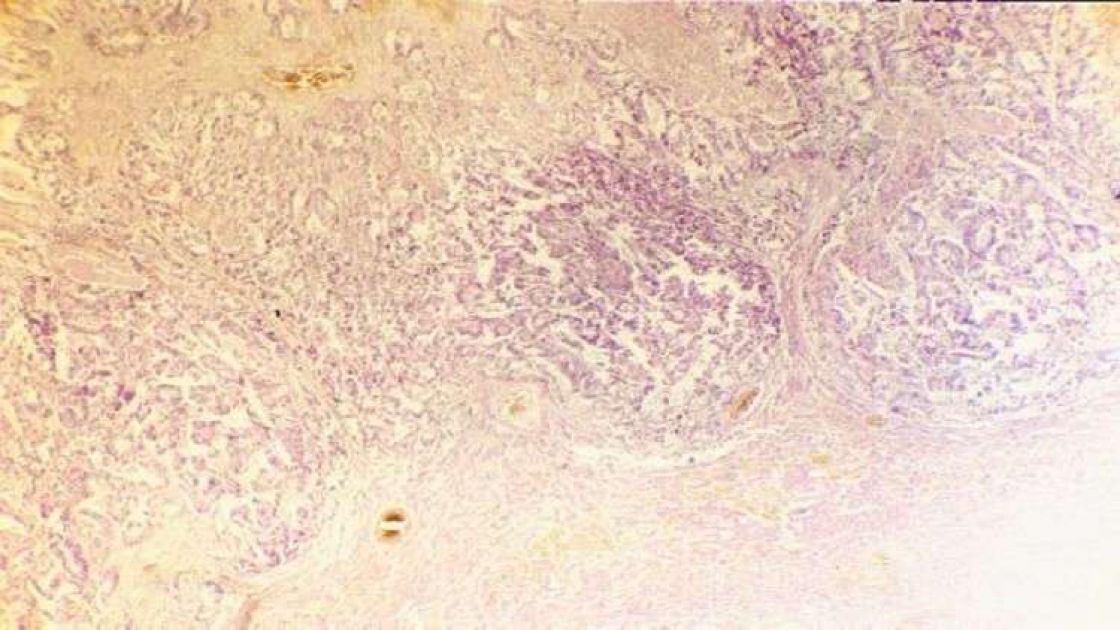

أظهرت نتائج دراسة أجراها علماء من بلجيكا أنه يمكن إجبار الجسم على مكافحة السرطان، ومن أجل ذلك يجب حجب آلية جزيئية تسبب كبت وظيفة جهاز المناعة.

ويفيد موقع MedicalXpress بأن العلماء اكتشفوا أن انخفاض مناعة الجسم يسببه تحرر بروتين السيتوكين-TGF-beta الذي يؤثر في الخلايا اللمفاوية (خلايا الجهاز المناعي)، ويجبرها على تخفيض نشاطها وعدم المساس بالخلايا السرطانية.

ومن أجل إجبار الجسم على مقاومة مكونات السرطان وتدميرها، من الضروري حجب هذا البروتين. وقد تمكن الباحثون من تحديد الجسم المضاد الذي يمكنه كبح هذا البروتين.